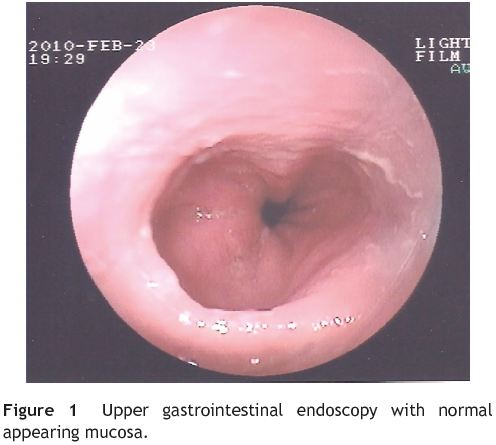

An upper gastrointestinal endoscopy was performed and revealed a normal appearing mucosa (Fig. 1). No biopsies were taken and she was diagnosed with non-erosive reflux disease. A 3 month trial with proton pump inhibitors at maximal doses was tried, but heartburn persisted and she began to complaining of intermittent solid-food dysphagia. Esophageal motility study with pH monitoring and barium radiography (Fig. 2) were performed and found to be normal.

Because of persistent heartburn that did not improve with appropriate medical treatment and taking in to account her past asthmatic history, eosinophilic esophagitis was suspected. Upper gastrointestinal endoscopy was then repeated and again revealed normal-appearing mucosa of esophagus, stomach and duodenum. Notwithstanding, biopsies were obtained from the proximal and distal esophagus. Histological examination revealed more than 20 intraepithelial eosinophils per high power field and multiple eosinophilic microabcesses (Fig. 3), both diagnostic of eosinophilic esophagitis. Biopsies from stomach and duodenum were also obtained and histological findings were normal.

Careful endoscopic examination may reveal ringed appearance, subtle furrows, whitish plaques, fragile crepe paper-like appearance and a small-caliber esophagus. Between 9% and 32% of patients with symptoms have normal endoscopic findings.1

Marked eosinophil infiltration in the esophageal epithelia (>20 eosinophils per high-power field) is the diagnostic Hallmark and samples should be obtained from proximal and distal esophagus,1-4 even in normal appearing mucosa in endoscopy.5 In our case report, we found normal appearing mucosa at endoscopy, but esophageal biopsies revealed marked eosinophilic infiltration. Recently, a prospective study conducted by Prasad G. et al. concluded that midesophageal biopsies taken from normal-appearing mucosa in patients with unexplained solid food dysphagia may diagnose eosinophilic esophagitis in about one in 10 cases.6